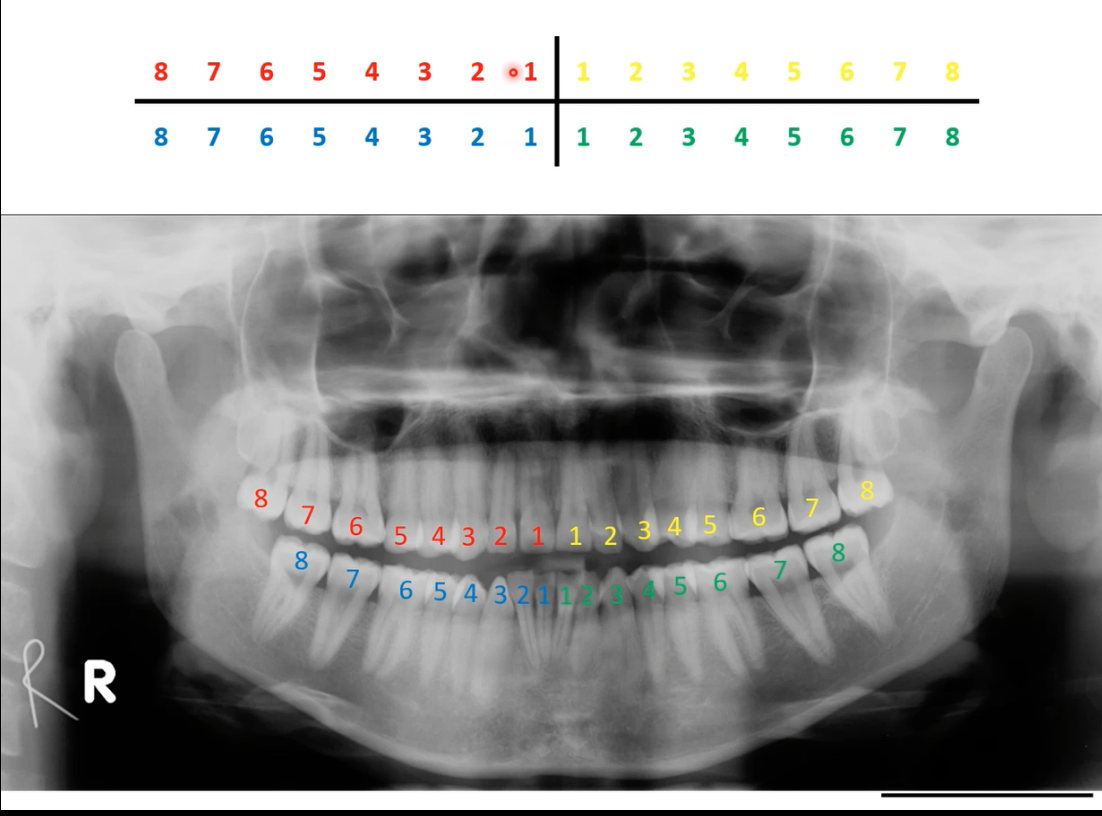

Charting - Palmer Notation

- Mouth divided into four quadrants

- Teeth are numbered 1-8 from central incisor to third molar

- ‘Letters and numbers system’

– Modification of Palmer

– LR3 to represent lower right canine.

standard approach is to start in upper right quadrant-ul-lower l-lower right